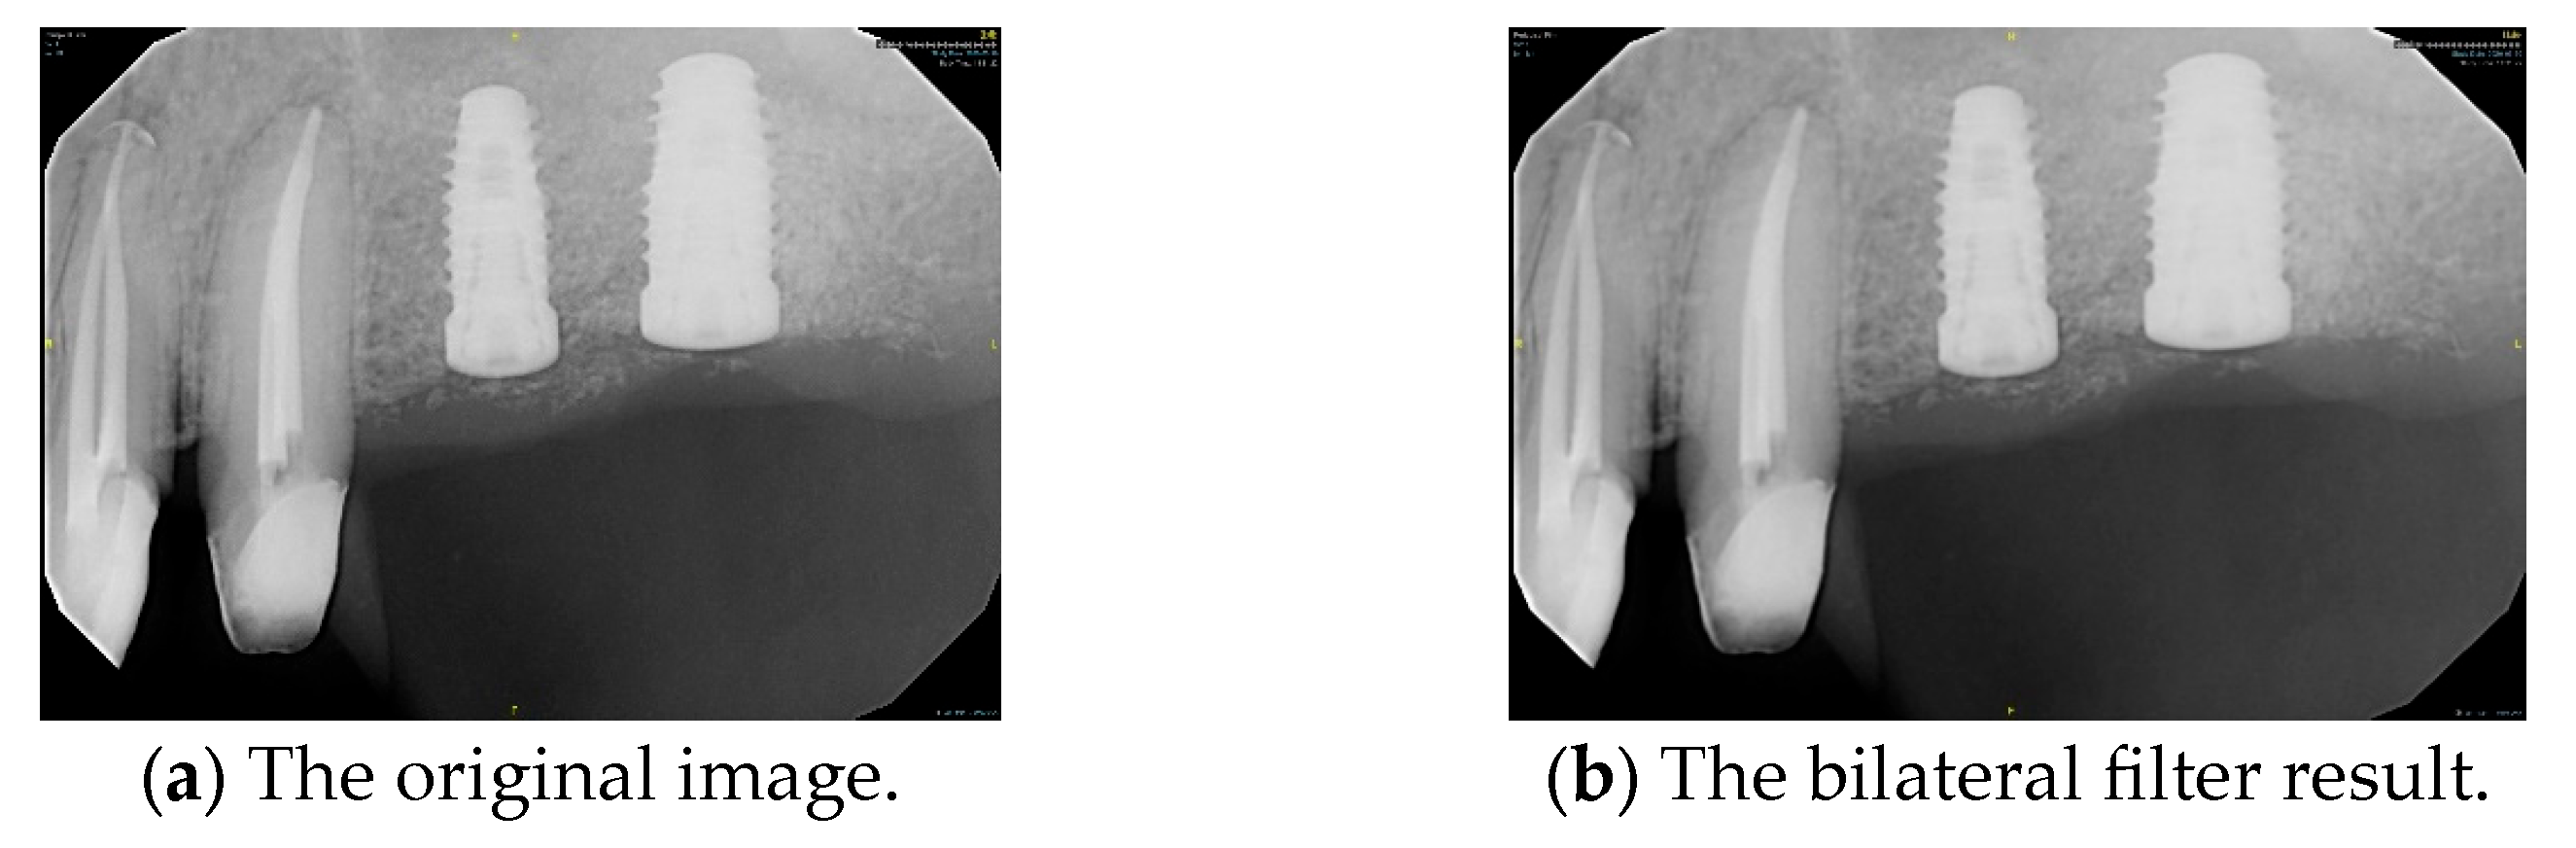

2.2.1. Bilateral Filter